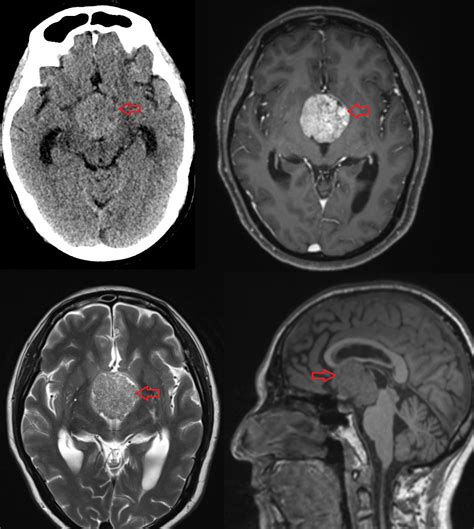

- MRI sken: Magnetická rezonancia umožňuje detailne zobraziť hypofýzu a identifikovať prípadné nádory.

Takmer všetky nádory hypofýzy sú benígne (nerakovinové) žľazové nádory nazývané adenómy. Aj keď sa nešíria do iných častí tela, môžu spôsobiť vážne zdravotné problémy, vrátane neplodnosti.

Nádory hypofýzy, ktoré nevytvárajú nadbytočné hormóny, sa nazývajú nefunkčné adenómy. Predstavujú asi 3 z 10 všetkých zistených nádorov hypofýzy. Obvykle sa vyskytujú ako makroadenómy a spôsobujú symptómy kvôli svojej veľkosti, keď tlačia na blízke štruktúry.